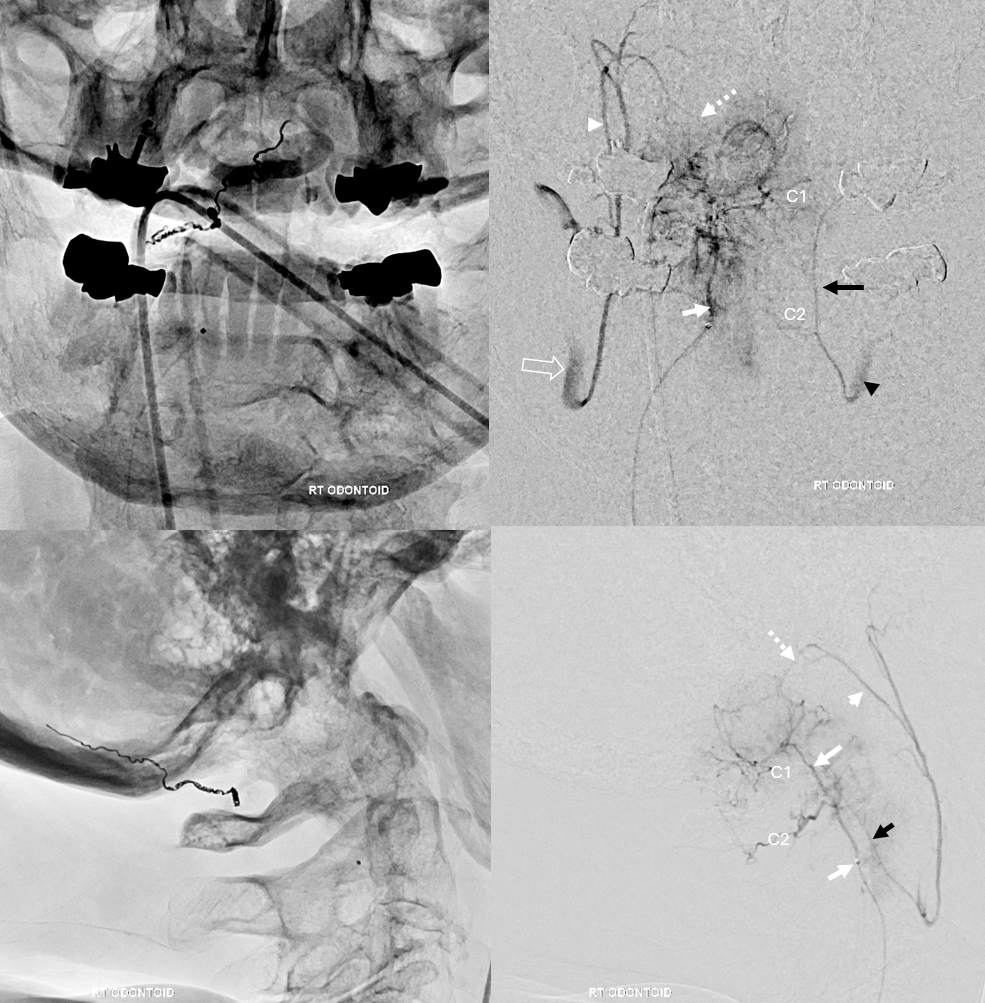

Another case study of odontoid arcade from another meningioma

The microcatheter (its relatively easy to catheterize the arcade given it favorable angle of origin from the vert) is in the arcade (solid white arrow, retrogradely visualizing the left portion of the arcade (black arrow) the left vert (black arrowhead). C2 and C1 epidural connections are present. The hypoglossal division (dashed white arrow and arrowhead) retrogradely opacify the ascending pharyngeal artery and the external carotid (open white arrow).

The same case, now with microcatheter position in the odontoid arcade. The same supply to the bone is noted, however note complete lack of spinal cord or radicular artery visualization. Direct spinal cord supply from the odontoid arcade is exceptionally rare, making it a relatively good embolization position in what is still a very treacherous area.